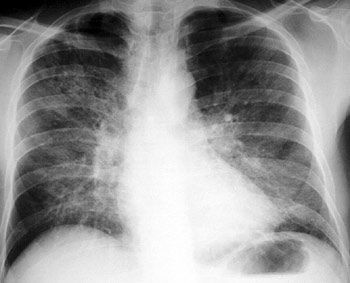

Question 17

Question

patología que se observa en la radiografía.

Answer

• enfisema

• atelectasia

• derrame pleural

• neumotorax